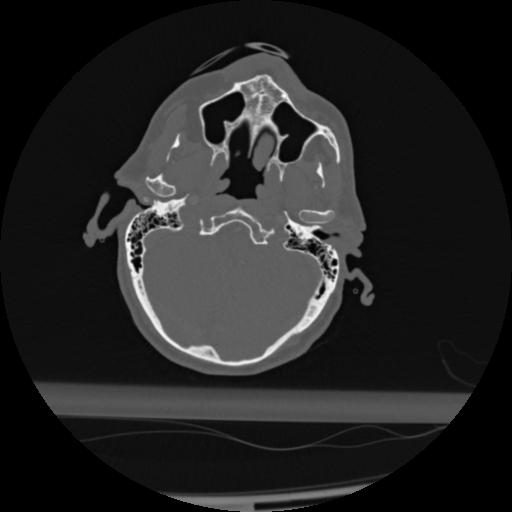

22 ANGIO,CE,Vol,0.5,ANGIO,,